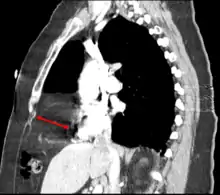

| Morgagni hernia seen on a chest radiograph. | |